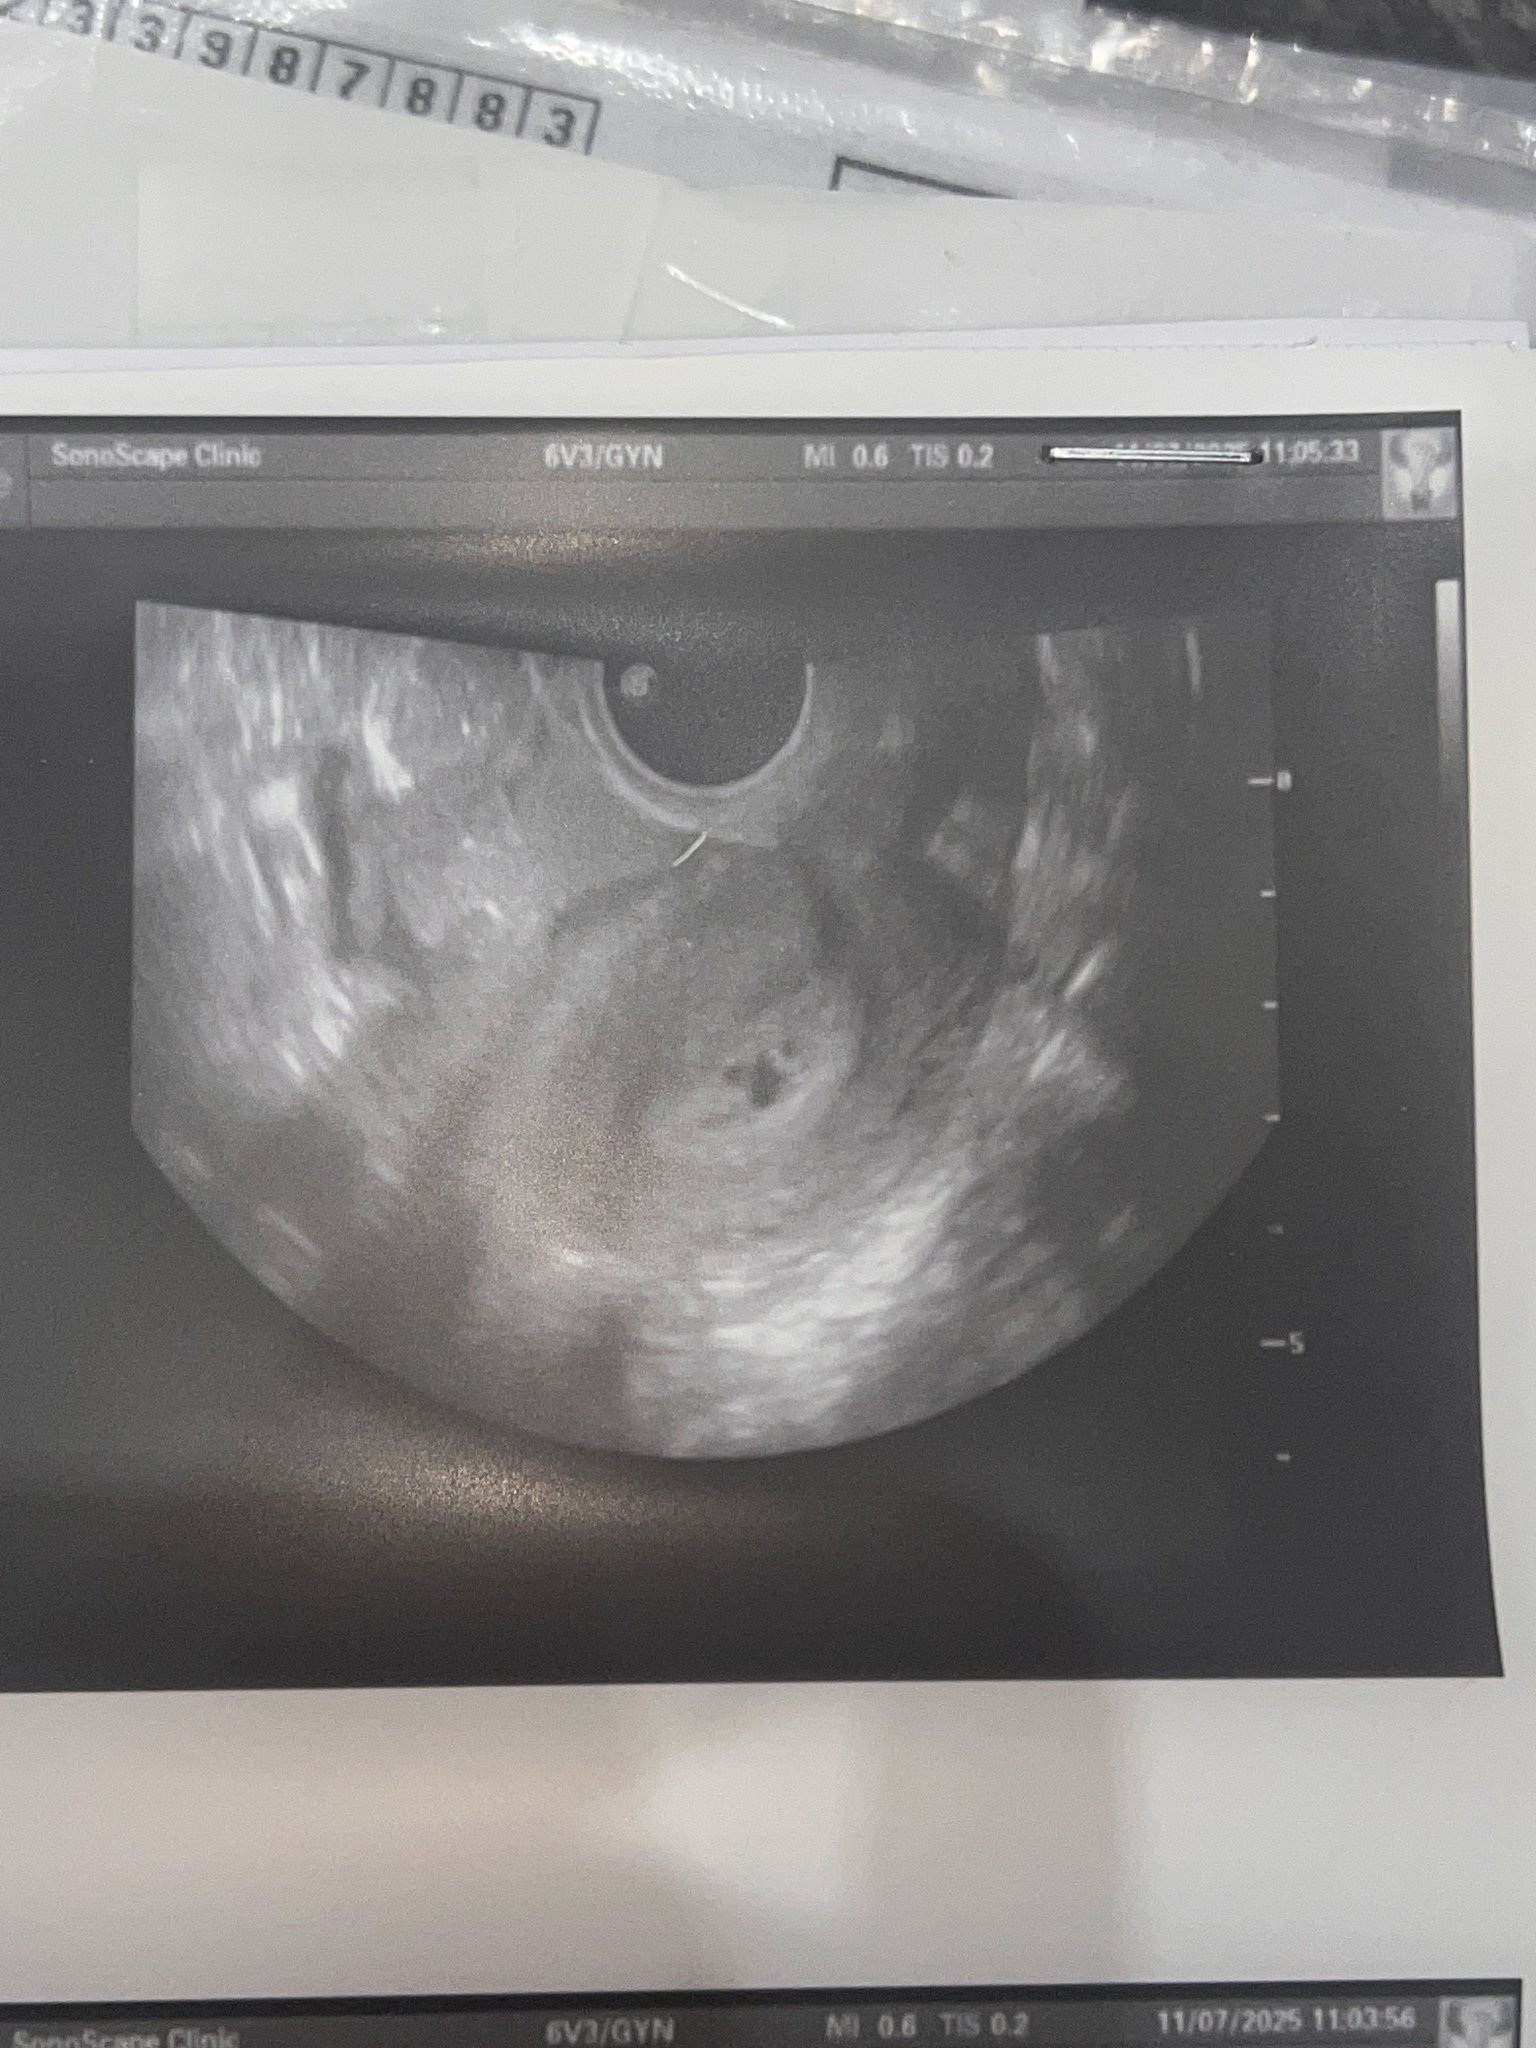

Днес бях на рутинен гинекологичен преглед

И АГ видя нещо приличащо на плоден сак и ме прати за кръвен тест който излезе отрицателен 0.100 IU както и предполагах понеже съм 11 след цикъл не мисля че е възможно тестове отрицателни а да се вижда на ехограф а и не правим опити за бебе в момента понеже лекувам бактерия

Мисълта ми е какво може да е това,опасно ли е на преглед съм отново след 2 седмици